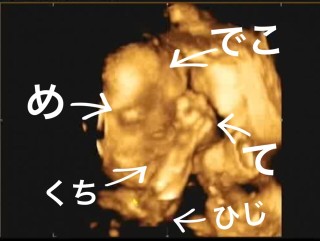

4Dエコーだけの日でした。最初は私のお腹にぺったり張り付いていて下向きでした。。 半分諦めてたけど、エコー技師さんが頑張ってくれたおかげで一応記念に残る写真が撮れました!出産後この写真とどのくらい似てるか気になるところです!